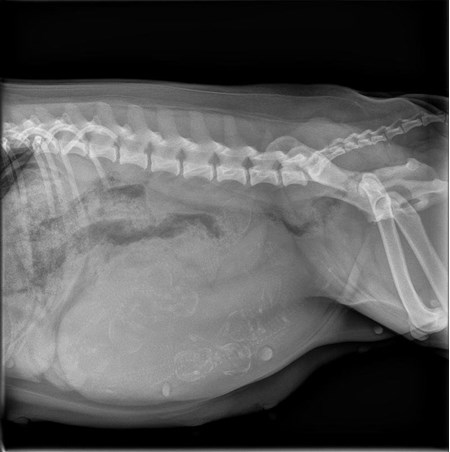

Deze RX-foto toont de ongeboren puppy's tijdens de zwangerschap.